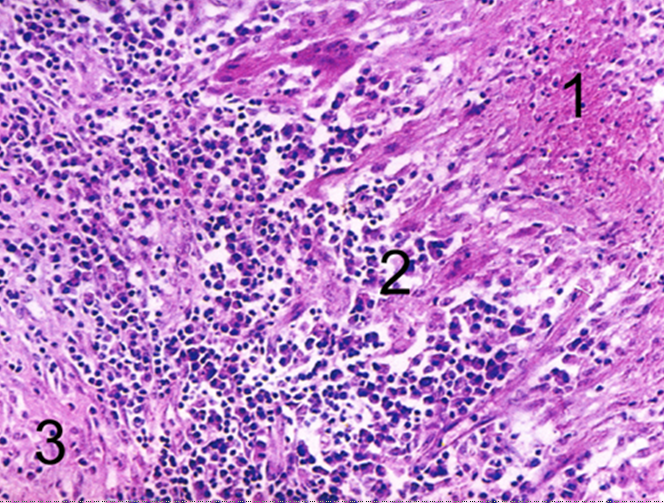

镜下:典型结核结节(tubercle)中央有干酪样坏死,周围由上皮样细胞、朗格汉斯巨细胞加上外周局部集聚的淋巴细胞和少量反应性增生的成纤维细胞构成。

壁厚可达1cm,镜下:镜下洞壁由内到外可分三层,内层 为干酪样坏死物(含多量结核杆菌),中层为结核性肉芽组织,外层为纤维结缔组织。